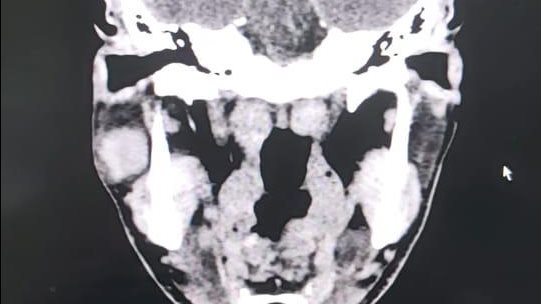

نجح فريق من قسم جراحة الوجه والفكين بمستشفى ادكو المركزى فى إجراء عملية دقيقة لإزالة ورم من الغدة النكافية " ورم حميد بالغدة النكافية من الفص السفلي "، وتم الحفاظ على العصب الوجهي السابع.

قام بإجراء العملية نخبة من جراحي قسم جراحة الوجه والفكين بالمستشفى، بقياده الدكتور وائل نمير استشاري جراحة الوجه و الفكين بالقسم، وأشراف الدكتور أحمد بلال رئيس القسم ، والدكتور محمود قاسم ، والدكتور ضياء يس أخصائيين جراحة الفم والأسنان، والدكتور عبد الرحمن عيسى استشاري التخدير ، وطاقم تمريض العمليات ، وفنيي التخدير.